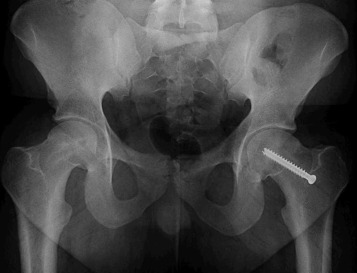

In this individual, who did not undergo prophylactic pinning, the left film shows the patient immediately following initial pinning, while the right film shows the final follow up. When comparing the left proximal femur at these two timepoints, it is evident that there is preserved proximal femoral anatomy between these two time points, with relative preservation of the femoral head-neck offset, femoral neck length, and positioning of the greater trochanter relative to the center of the femoral head.